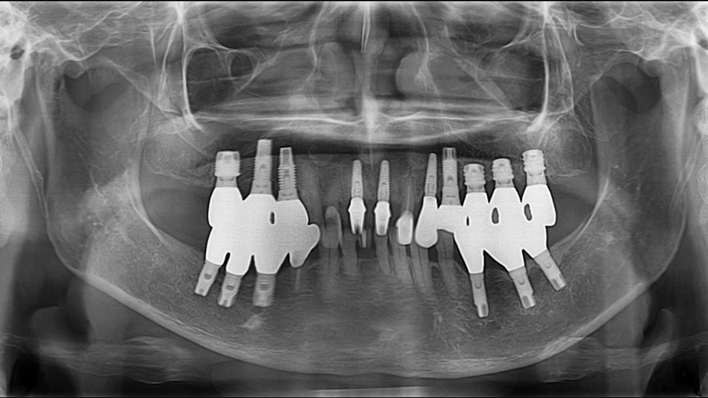

Clinical case: : Immediate loading of lower molars using R2Gate prefabricated 3D-printed provisional restoration

- Courtesy of Dr. Sam Omar, Egypt -